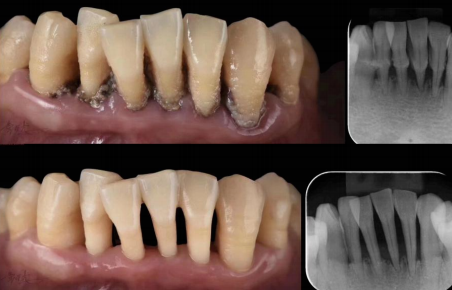

1、功率越小舒适度越高,在牙周治疗的过程中切勿追求速度让患者治疗舒适体验下降。我们应该根据患者的耐受度和牙结石大小及硬度的不同选择可以去除牙结石的最小功率为患去除牙结石。

2、调整合适的水量,以达到给钛合金工作尖降温的目的,并且可以有效的对牙周及牙周袋内的垃圾形成冲洗。什么样的水量最合适。调整好需要的功率后调整水量,踩下脚踏开关在空载无负荷的状态下,钛合金工作尖上的水滴可以到达工作尖尖端并形成水滴滴落为宜。负载工作时水滴会到达钛合金工作尖尖端后爆裂形成雾化。只有这样才既可以冷却钛合金工作尖又可以有效的对牙齿牙周形成冲洗。

3、不同的钛合金工作尖震幅轨迹不同。根据洁牙的位置不同正确的选择合适的钛合金工作尖。选择钛合金工作尖适当的面,配合适当的操作手法实现无痛牙周治疗。

4、手法:持洁牙手柄的手必须要有支点,操作时医生手腕不可移动和发力,用大拇指、食指、中指、发力略向内拉,每次移动范围不操过两毫米。手把持住手柄使钛合金工作尖贴住牙结石或者牙齿表面即可,不可以施加压力。利用超声波震动击碎牙结石。